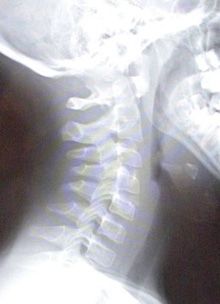

The patient’s vital signs are normal, but she has a low-grade fever (temperature, 99.7°F). Eye findings are normal. Her oropharynx appears remarkably normal, and there is no drooling, stridor, trismus, or abnormal voice. She does, however, have a stiff neck with symmetric limited range of motion in all planes and in all directions. Plain films of the neck are done (Figure 1).

Radiographs of this patient demonstrate widening of the prevertebral soft tissues: this finding is consistent with a retropharyngeal abscess (see Figure 1). Although at first glance the soft tissues may appear normal, there should actually be a step-off around C3-C4, which is not noted in this film. Normal prevertebral soft tissues should measure less than 6 mm at C2 and less than 22 mm at C6. A normal x-ray film is provided for comparison (Figure 2).

Figure 1 shows widening of the prevertebral soft tissues, a finding consistent with a

retropharyngeal abscess.

Normal prevertebral soft tissues should measure less than 6 mm at C2 and less than 22 mm at C6, as shown in Figure 2.